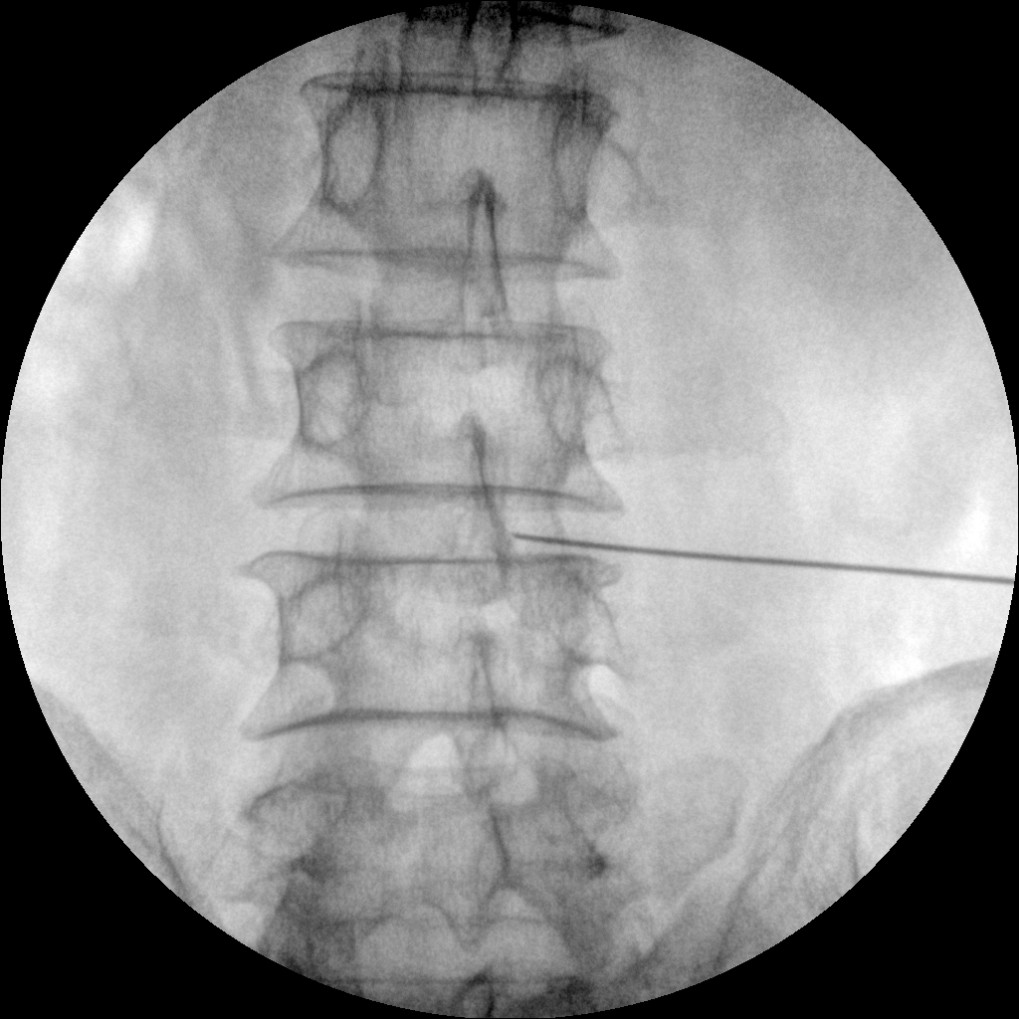

●經(jīng)典影像工作站,可隔室操作避免輻射

●全數(shù)字化百萬(wàn)像素影像系統(tǒng),圖像清晰

●靈活的C臂機(jī)架設(shè)計(jì),滿足臨床大范圍運(yùn)動(dòng)

●臨床功能豐富,具備脈沖控制、數(shù)字?jǐn)z影、自動(dòng)透視等